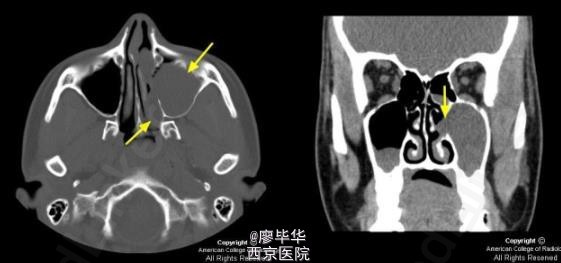

患者,20岁,女性,因有鼻塞、流脓涕并伴有头晕症状就诊。

查体可见患者有鼻塞、流脓涕并伴有头晕症状,检查可见鼻粘膜慢性充血肿胀并伴有脓性分泌物 辅查 CT